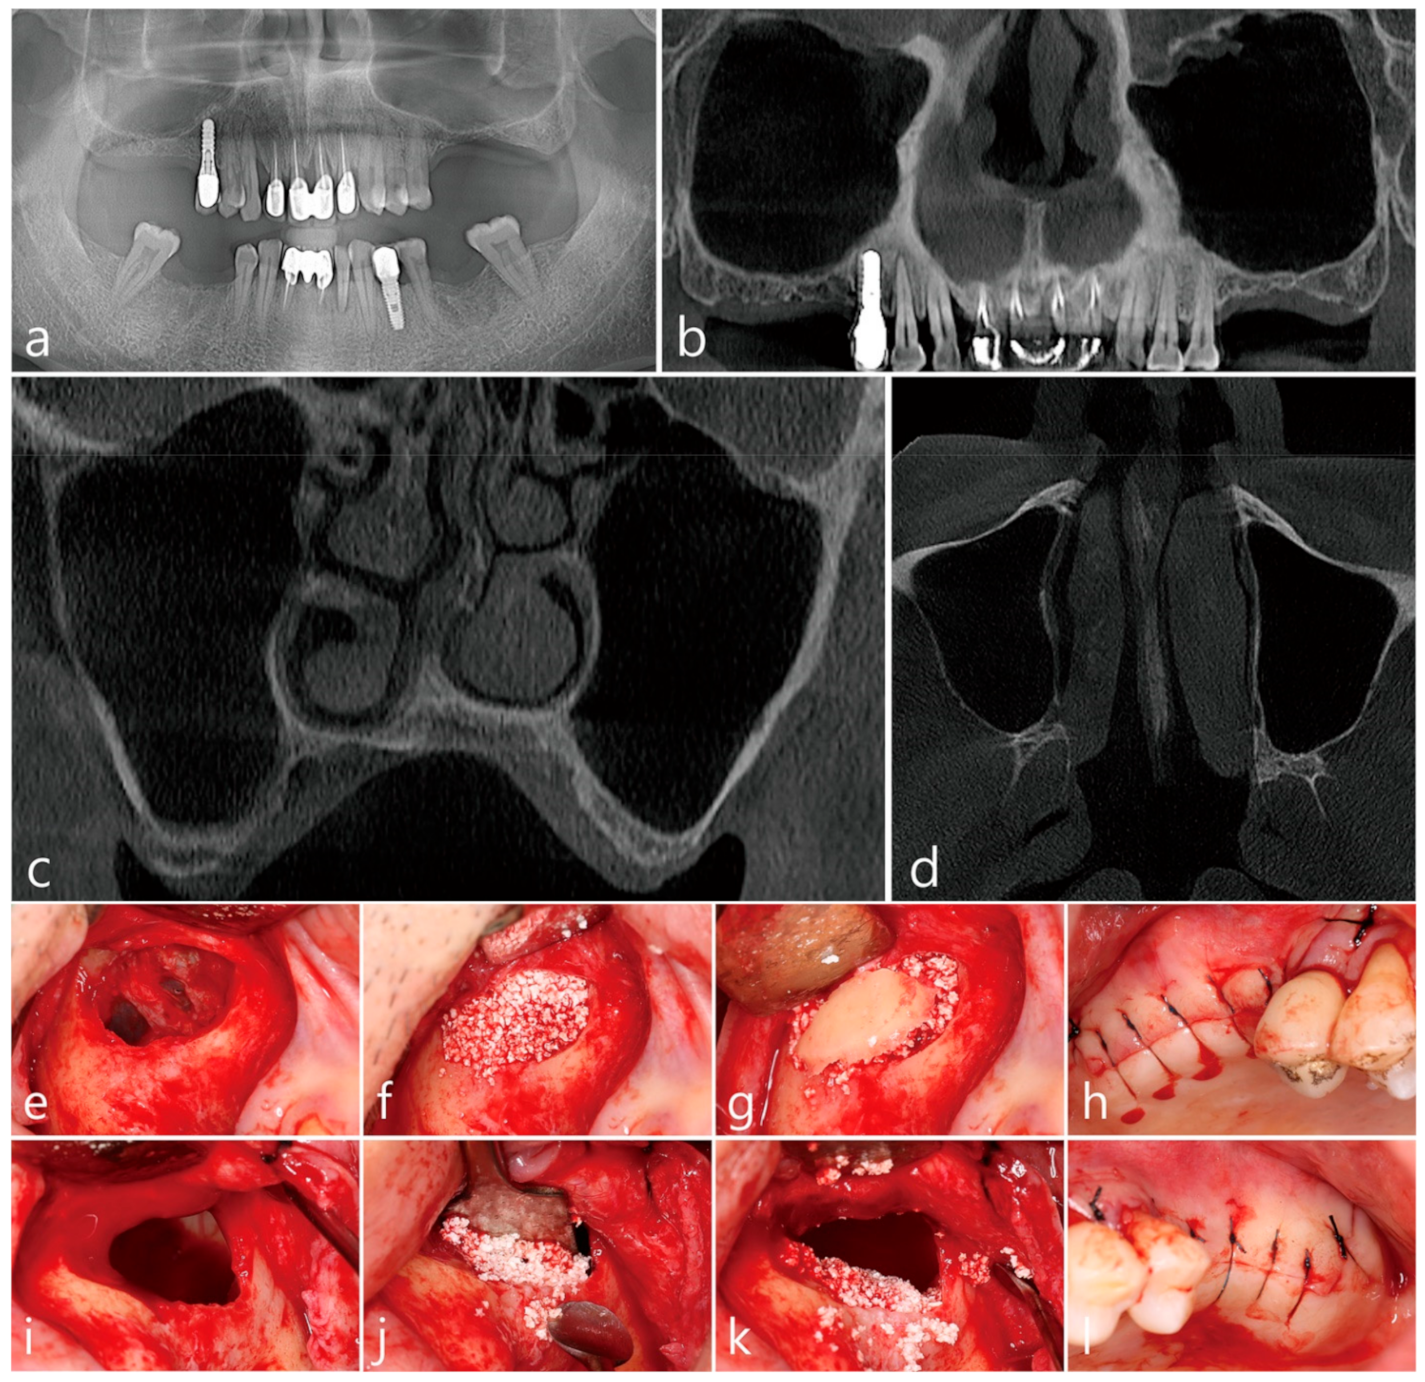

Sinus augmentation using the lateral window technique in complex cases Lateral Window Sinus Lift Technique Pdf A simplified technique for preparation of the window and elevation of the sinus membrane using conventional instruments is described for the practitioner to prepare the schneiderian. The maxillary sinus augmentation technique is largely divided into a lateral approach method to form a window on the side wall bone of. A technique for bone augmentation in this region by preparing a. Lateral Window Sinus Lift Technique Pdf.